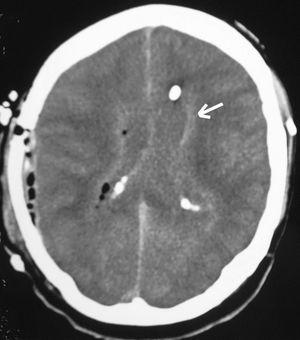

Al octavo día ingresó en la Unidad de Cuidados Intensivos en situación de coma (Glasgow Coma Scale [GCS] 5 puntos). Tras intubación y estabilización hemodinámica se realizó TAC craneal con contraste, observándose persistencia de hidrocefalia a pesar de válvula ventriculoperitoneal. La analítica de ingreso fue: hemoglobina 10,8 g/dl, leucocitos 7.200/mm3, plaquetas 225.000/mm3; sodio 147 mEq/l, potasio 6,4 mEq/l, glucemia 148 mg/dl y creatinina 4,2 mg/dl. En el LCR: hematíes 7.200 células/mm3, 400 células/mm3 l (95% polimorfonucleares), glucosa 60 mg/dl y proteínas 814 mg/dl. Se aisló, L. monocytogenes sensible a ampicilina y vancomicina. Se realizó craneotomía temporal derecha con exéresis de absceso cerebral sin retirarse la válvula ventriculoperitoneal. En el cultivo creció el mismo microorganismo. Pocas horas después el paciente presentaba GCS de 3 puntos, pupilas medias arreactivas. En la TAC craneal (fig. 2) se apreciaba ocupación ventricular por material de similar densidad que el parénquima cerebral. Se drenó material purulento semejante al evacuado del absceso por punción del reservorio de la válvula. En situación de shock séptico se objetivaron signos clínicos de muerte encefálica, que se confirmó mediante eco-doppler transcraneal. El enfermo falleció a las 24 horas de la intervención.

Figura 2. Ocupación de los ventrículos laterales.